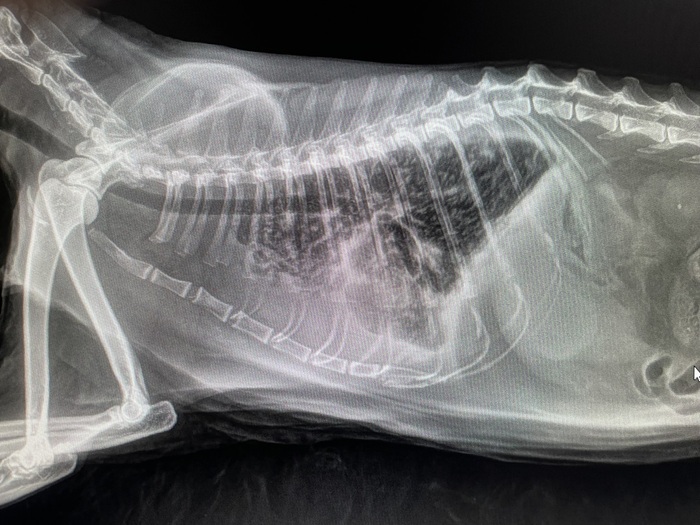

Дано: возрастная кошка с длительным ринитом.

Пришли на прием 13.10 с формулировкой «гноится глазик». Я увидел их 14.10 и всё же уговорил пойти на кт, а там абсцесс за левым глазом, фронтит (забиты и лобные пазухи, и носовые ходы).

После проводим фронтотомию - по сути, бурим дырку в лобную пазуху для промывания и вымывания всего скопившегося гноя.

Промыв всё большим количеством тёплого стерильного физ.раствора, зашиваем всё. Плюсом удаляем назофарингеальный полип.